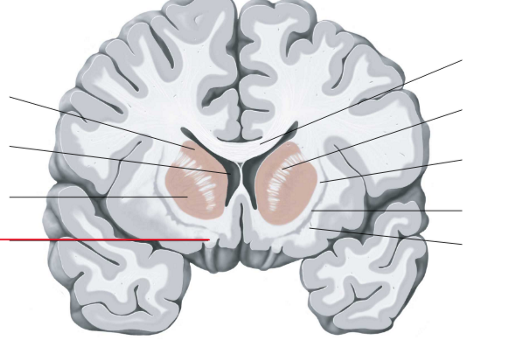

nucleus caudatus

putamen

capsula interna (corona radiata)

laterale ventrikels (I en II)

septum pellucidum